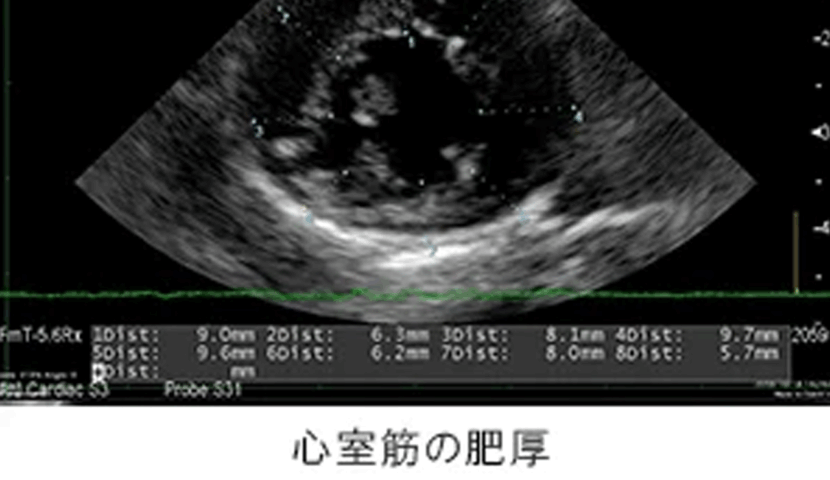

胸部レントゲン検査にて肺野の不透過性亢進像を確認。心臓超音波検査にて、心室筋の肥厚を確認。肥大型心筋症と診断。

胸部レントゲン検査にて肺野の不透過性亢進像を確認。心臓超音波検査にて、心室筋の肥厚を確認。肥大型心筋症と診断。